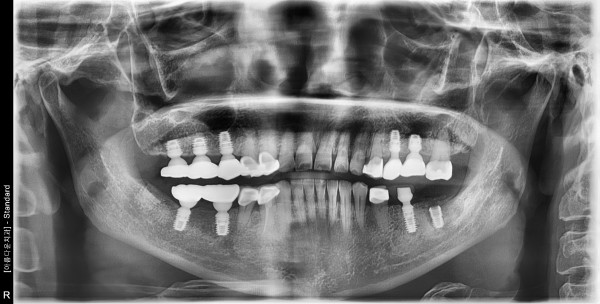

57세 여/ 상ㆍ하악 구치부 발치, 치조골 이식술 후 임플란트 식립